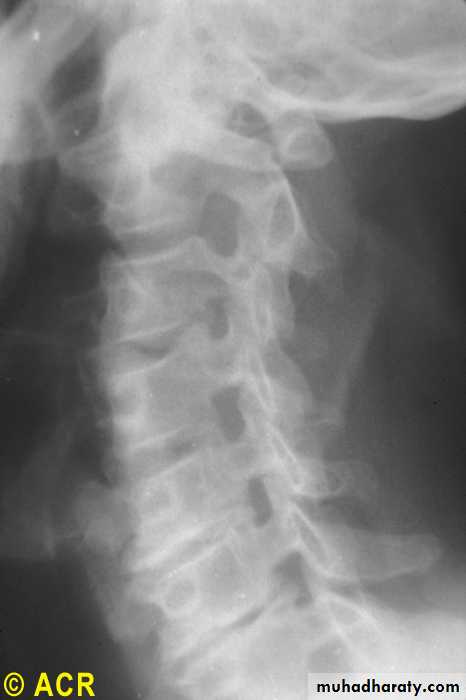

Osteoarthritis:cervicalvertebrae,foraminalencroachment